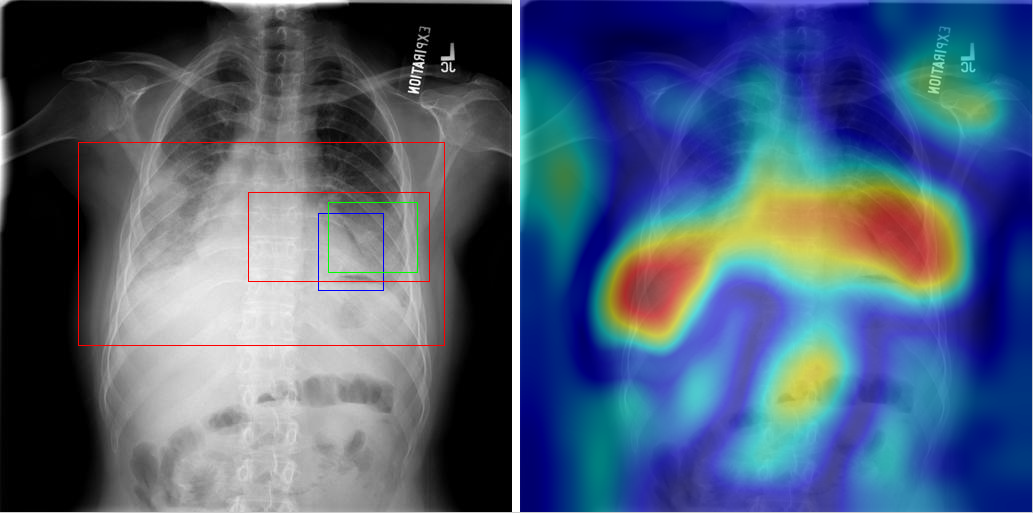

Table 8 to Table 15 illustrate localization results from each of 8 disease classes together with associated report and mined disease keywords. The heatmaps overlay on the original images are shown on the right. Correct bounding boxes (in green), false positives (in red) and the groundtruth (in blue) are plotted over the original image on the left.

In order to quantitatively demonstrate how informative those heatmaps are, a simple two-level thresholding based bounding box generator is adopted here to catch the peaks in the heatmap and later generated bounding boxes can be evaluated against the ground truth. Each heatmap will approximately results in 1-3 bounding boxes. We believe the localization accuracy and AFP (shown in Table 7) could be further optimized by adopting a more sophisticated bounding box generation method, e.g. selective search [47] or Edgebox [18]. Nevertheless, we reserve the effort to do so, since our main goal is not to compute the exact spatial location of disease patterns but just to obtain some instructive location information for future applications, e.g. automated radiological report generation. Take the case shown in Table 8 for an example. The peak at the lower part of the left lung region indicates the presence of “atelectasis”, which confer the statement of “…stable abnormal study including left basilar infilrate/atelectasis, …” presented in the impression section of the associated radiological report. By combining with other information, e.g. a lung region mask, the heatmap itself is already more informative than just the presence indication of certain disease in an image as introduced in the previous works, e.g. [42].

Radiology report Keyword Localization Result

findings include: 1. left basilar atelectasis/consolidation. 2. prominent hilum (mediastinal adenopathy). 3. left pic catheter (tip in atriocaval junction). 4. stable, normal appearing cardiomediastinal silhouette. impression: small right pleural effusion otherwise stable abnormal study including left basilar infiltrate/atelectasis, prominent hilum, and position of left pic catheter (tip atriocaval junction). Effusion; Infiltration; Atelectasis [Uncaptioned image]

Table 8: A sample of chest x-ray radiology report, mined disease keywords and localization result from the “Atelectasis” Class. Correct bounding box (in green), false positives (in red) and the ground truth (in blue) are plotted over the original image.